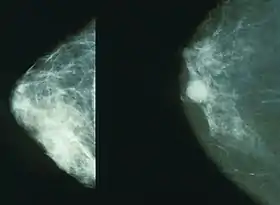

Mammography

Mammography is a common screening method, since it is relatively fast and widely available in developed countries. Mammography is a type of radiography used on the breasts. It is typically used for two purposes: to aid in the diagnosis of a woman who is experiencing symptoms or has been called back for follow-up views (called diagnostic mammography), and for medical screening of apparently healthy women (called screening mammography).[8]

Mammography is not very useful in finding breast tumors in dense breast tissue characteristic of women under 40 years.[9][10] In women over 50 without dense breasts, breast cancers detected by screening mammography are usually smaller and less aggressive than those detected by patients or doctors as a breast lump. This is because the most aggressive breast cancers are found in dense breast tissue, which mammograms perform poorly on.[9] The European Commission's Scientific Advice Mechanism recommends that MRI scans are used in place of mammography for women with dense breast tissue.[6]

Women who agree to be screened have their breasts X-rayed on a specialized X-ray machine. This exposes the woman's breasts to a small amount of ionizing radiation, which has a very small, but non-zero, chance of causing cancer.

The X-ray image, called a radiograph, is sent to a physician who specializes in interpreting these images, called a radiologist. The image may be on plain photographic film or digital mammography on a computer screen; despite the much higher cost of the digital systems, the two methods are generally considered equally effective. The equipment may use a computer-aided diagnosis (CAD) system.

There is considerable variation in interpreting the images; the same image may be declared normal by one radiologist and suspicious by another. It can be helpful to compare the images to any previously taken images, as changes over time may be significant.

Breast density

Breasts are made up of breast tissue, connective tissue, and adipose (fat) tissue. The amount of each of the three types of tissue varies from person to person. Breast density is a measurement of relative amounts of these three tissues in breasts, as determined by their appearance on an X-ray image. Breast and connective tissues are radiographically denser (they produce a brighter white on an X-ray) than adipose tissue on a mammogram, so a person with more breast tissue and/or more connective tissue is said to have greater breast density. Breast density is assessed by mammography and expressed as a percentage of the mammogram occupied by radiologically dense tissue (percent mammographic density or PMD).[22] About half of middle-aged women have dense breasts, and breasts generally become less dense as they age. Higher breast density is an independent risk factor for breast cancer. Further, breast cancers are difficult to detect through mammograms in women with high breast density because most cancers and dense breast tissues have a similar appearance on a mammogram. As a result, higher breast density is associated with a higher rate of false negatives (missed cancers).[23] Because of the importance of breast density as a risk indicator and as a measure of diagnostic accuracy, automated methods have been developed to facilitate assessment and reporting for mammography,[24][25] and tomosynthesis.[26]